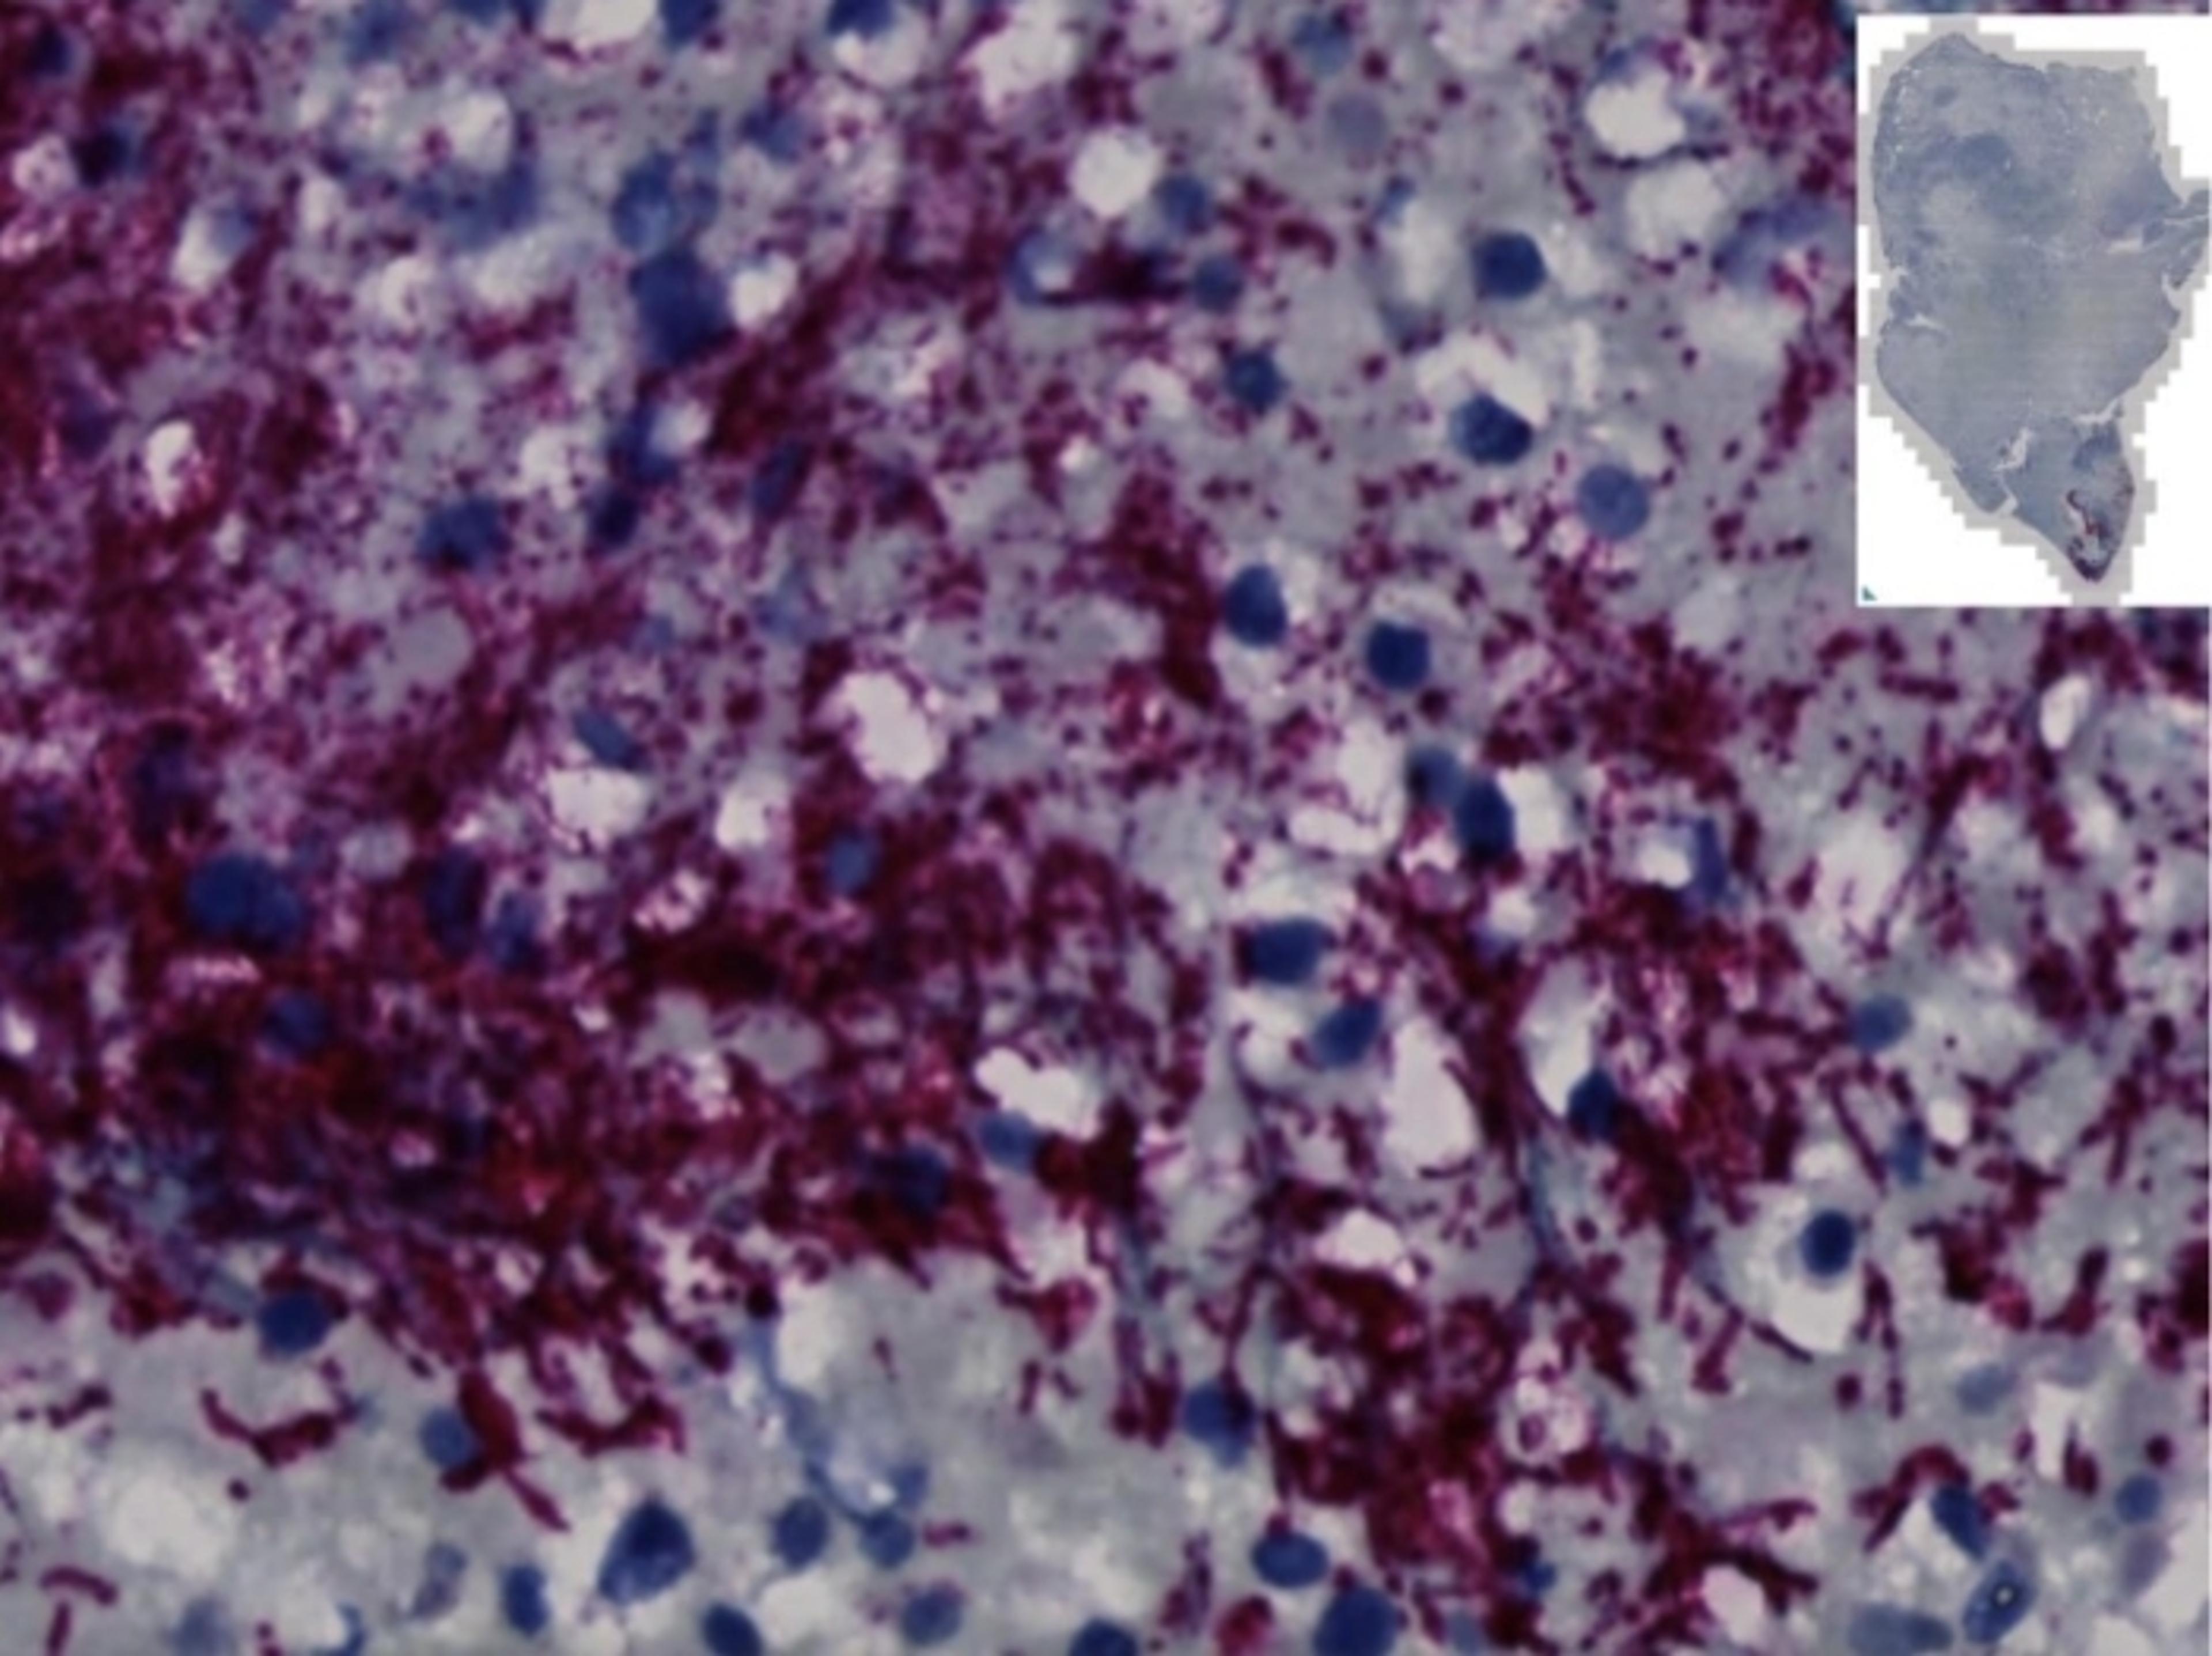

Bacteria subtype could assist in early colorectal cancer screening

A study suggests that a subtype of Fusobacterium nucleatum underlies colorectal cancer growth in humans and could be useful in screening and treatments